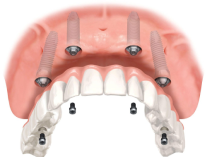

В чём заключается технология All-on-4

Мы устанавливаем 4 импланта и несъёмный протез на всю челюсть за 1 приём

Имплантация All-on-4:

4 импланта + несъёмный протез за 1 день